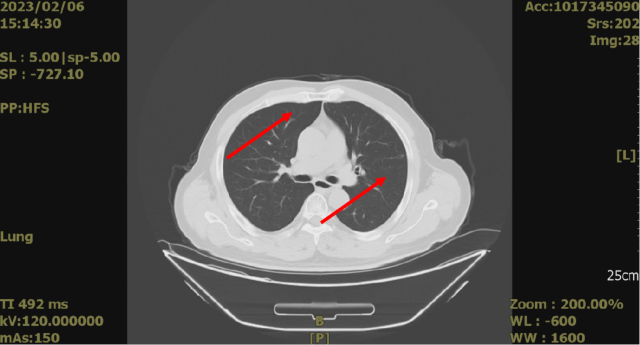

舒尼替尼治疗后,2023-02-06 复查 CT

1. 结合临床,左肾癌术后;考虑肝转移,较前缩小

2. 双肺多发结节,较前(2022-08-15)缩小。

2023-02-06 CT